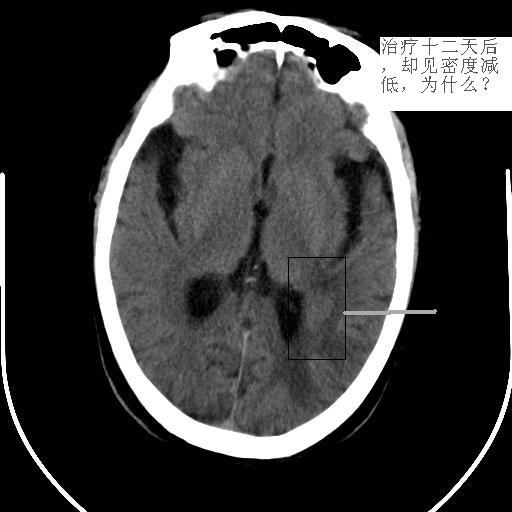

病灶平扫ct值约38hu,强化后明显强化,ct值约63hu,有一层ct值约72hu,病史:病人,男75,血压120/75,不高,头晕12天,平时体健,当时曾作胸x线片,正常。腹部ct,肝多发囊肿。经治疗(林格液+甘露醇)未用营养液及化疗药,当时诊断转移瘤。12天复查片如下

真的不可思议啊,难道是我们的确诊断错误,是颅内多发性出血灶?但为何前次会明显强化呢?

不对,还做过什么治疗?病人连做了2次ct扫描,是不是淋巴瘤受x线照射后病灶缩小、吸收的原因?不能大意,建议跟踪复查。

我还是坚持原来的意见,首先考虑淋巴瘤。

这么长时间了,怎么还没有结果?怎么误诊的?第二次ct见高密度灶消失,不过第一次有强化不应该是出血,还是考虑淋巴瘤。

病灶短期内经过治疗有明显变化。脑桥左侧部可见腔隙性脑梗塞,左枕叶病变考虑出血性脑梗塞可能性大。